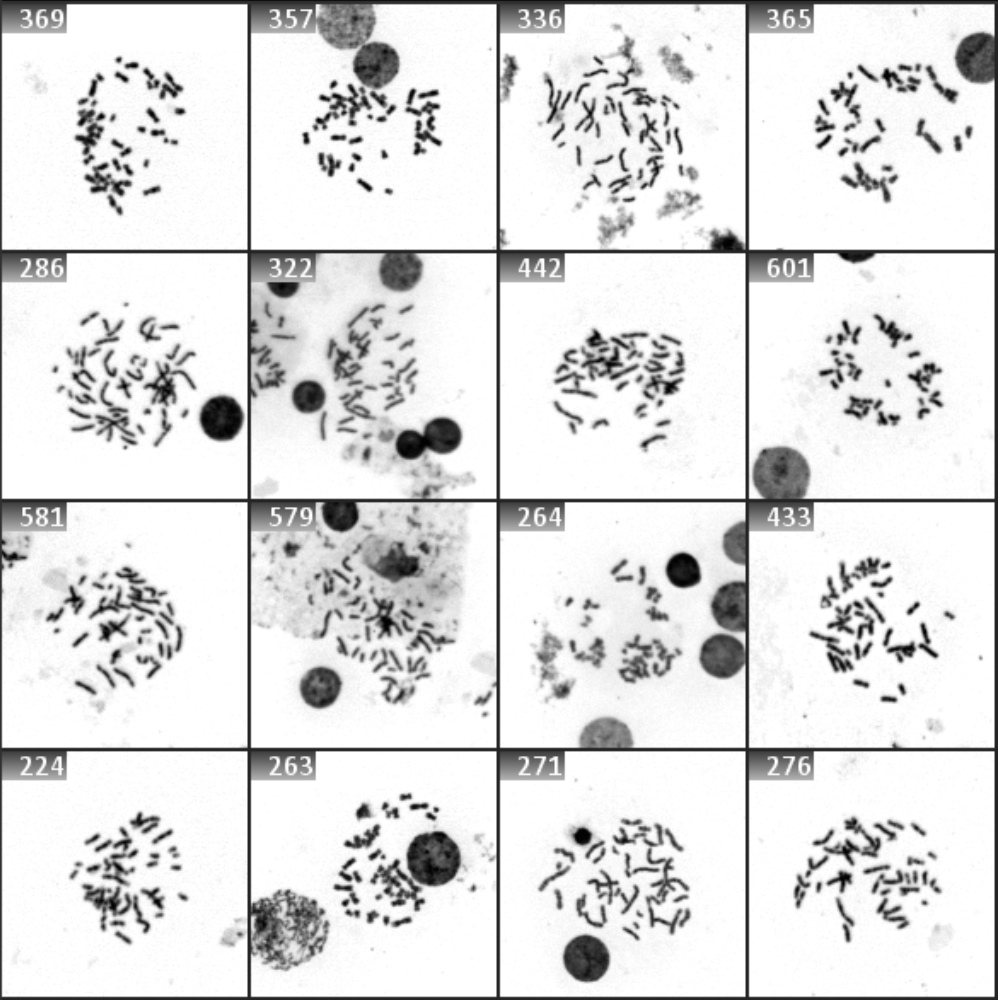

Recognized objects, e.g. metaphases, are automatically displayed in a real-time gallery during the search process. They can be easily relocated by clicking on the corresponding gallery image for detailed examination. To capture high-resolution images, metaphases can be selected either interactively or automatically, based on the user’s workflow settings. In the interactive method, the user simply selects metaphases of choice using the mouse. Alternatively, search parameters can be configured to assign user-defined quality values to the metaphases, allowing for the automatic selection of the top-rated objects. Additionally, a few randomly selected objects can also be captured. Once acquired, the images are immediately accessible to any connected workstation.

Once the Metafer Platform Software is installed in your lab, you can configure workflows to detect metaphases on slides automatically. Metafer offers two object detection methods. The first is based on classic machine learning algorithms, which quickly identify metaphases and display them as gallery images after the search. This method is fast and commonly used by many customers. More recently, the platform has also incorporated Deep Neural Networks (DNN), which can be trained to identify metaphases from images classified by the users. Although this method is a bit slower than the traditional algorithms, our customers report that it provides more accurate and specific results. The choice between these two methods depends on various factors, and during the customization process, our application specialists will assist you in developing the most appropriate workflow for your laboratory.